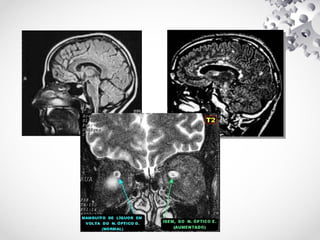

DÉFICIT COGNITIVO / ALZHEIMER

PERDA DE MEMÓRIA

• PARA APROFUNDAR NO ESTUDO DESSA INDICAÇÃO

UTILIZAMOS UMA SEQUÊNCIA ADICIONAL E UMA

SEQUÊNCIA FUNCIONAL QUANDO SOLICITADO,ALÉM DO

PROTOCOLO BÁSICO.

• SEQUÊNCIA ADICIONAL

– T2 NO PLANO CORONAL ANGULADO PARA O HIPOCAMPO

Hipocampo é uma estrutura localizada nos lobos temporais do

cérebro humano, considerada a principal sede da memória, esta

estrutura é muito importante para converter a memória a curto

prazo em memória a longo prazo.

HIPOCAMPO VISTA CORONAL

HIPOCAMPO VISTA SAGITAL

HIPOCAMPO VISTA AXIAL